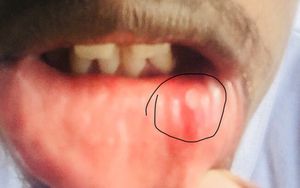

Recurrent lesion in the mucosa for several times

DDx: aphthous ulcer , herps simplex infection.

Aphthus ulcer

Behcet disease, oral aft